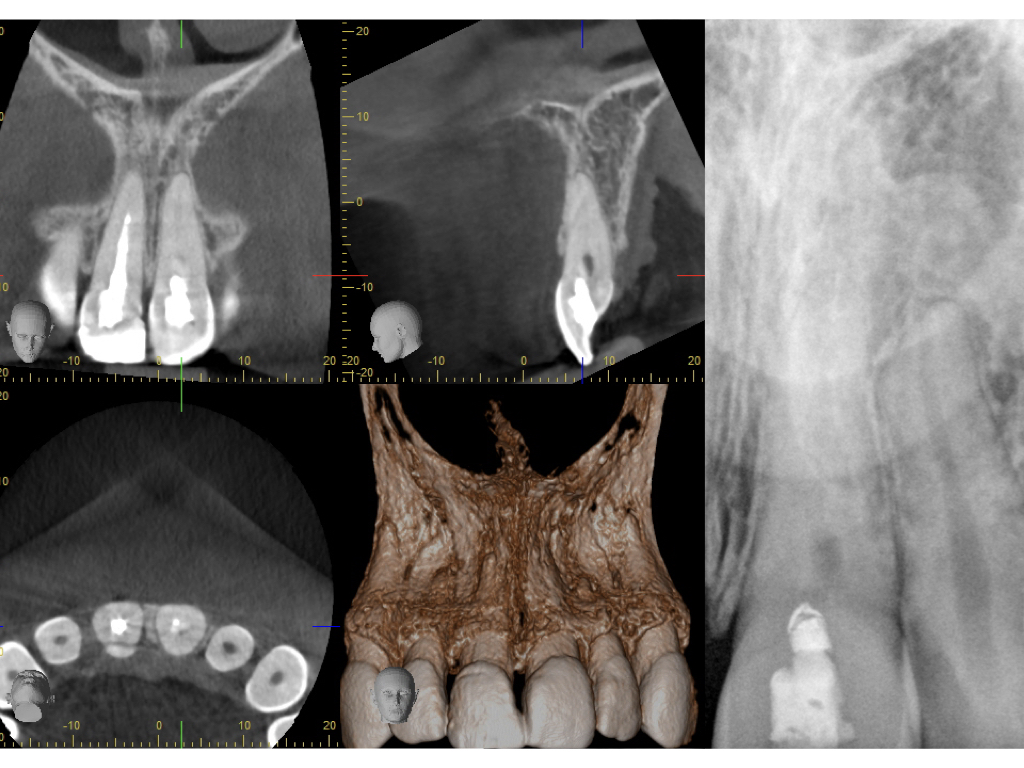

Schmerzfall (2)